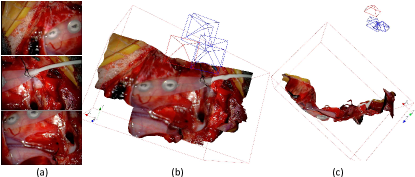

In the third set of experiments, we obtained intraoperative stereo laparoscopy images from a uretheroplasty procedure. Prior to resecting the urethral constriction, the urethra was exposed to identify the extent of the constriction. Thereafter, the authors scanned the exposed surgical area using a stereo laparoscope (Karl Storz Inc., model TipCam 26605AA) by moving the laparoscope slowly along the urethra. The interlaced video was captured and recorded using a video capture program in OpenCV. Fig. 12 shows the results of the surface mosaicking algorithms of the exposed urethra. The figure shows a high-resolution 3D mosaicked surface model of the urethra and the surrounding structures. The fourth set of experiments were conducted with the same stereo laparoscope and the data was collected during a spine surgery, as shown in Fig. 13. The spine bone was scanned by the Karl Storz stereo laparoscope after it was exposed. The estimated camera trajectories are smooth, which qualitatively prove that our method is accurate.